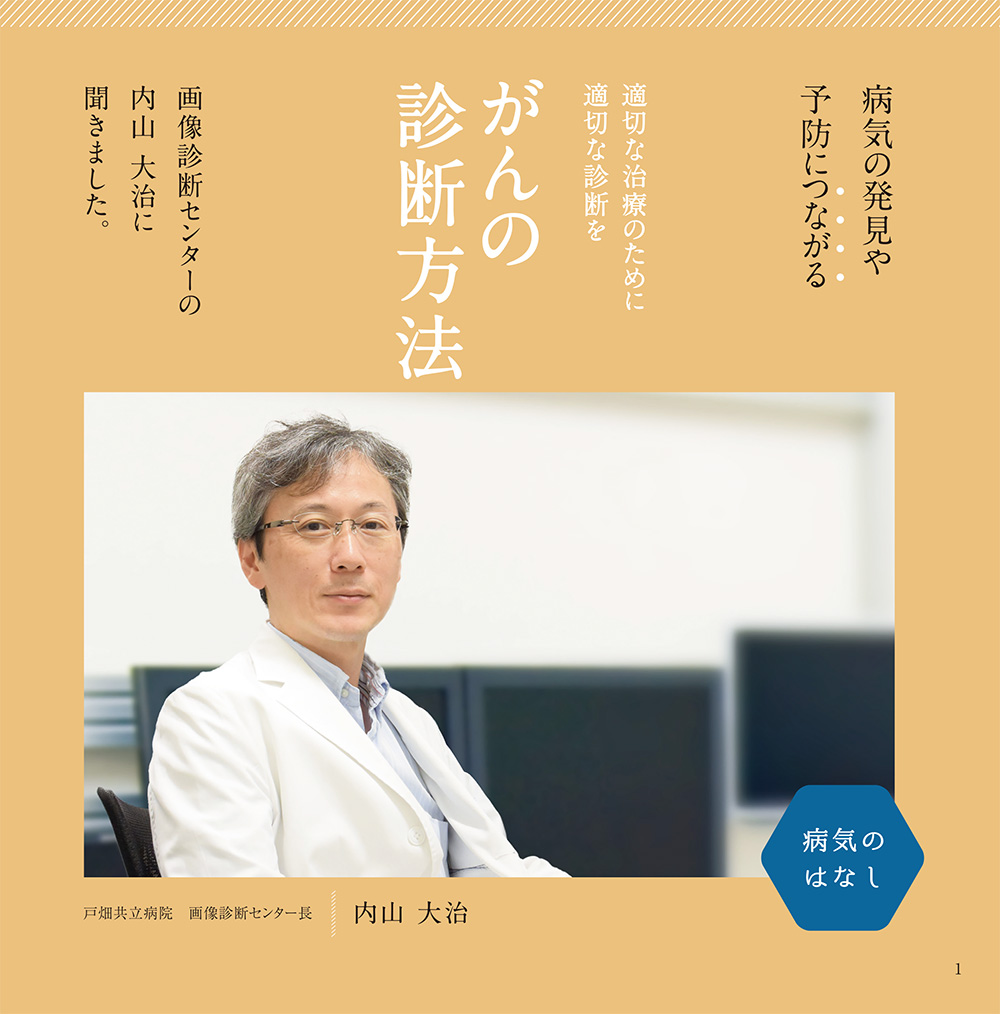

病気のはなし

病気の発見や予防につながる

適切な治療ために適切な診断を

がんの診断方法

画像診断センターの内山大治に聞きました

最大の治療効果を得るために

ほとんどの病気に対して適切な治療を行うためには、適切な診断を必要としています。がん診療においても同様で、各臓器に対する治療を適切に行うためには、がんの種類や広がりを正確に診断する必要があります。これは、最大の治療効果を得るために、治療の体への負担を最小限にし、がんとの共生社会を目指しているためです。したがって、がんの診断には主治医の問診・診察以外に、血液検査、内視鏡検査・内視鏡診断、画像検査・画像診断、病理検査・病理診断など、多くの検査が行われ、種々の検査の組み合わせによる総合的な診断が必要です。ここでは、私が専門とする放射線診断学についてご紹介したいと思います。

ほとんどの病気に対して適切な治療を行うためには、適切な診断を必要としています。がん診療においても同様で、各臓器に対する治療を適切に行うためには、がんの種類や広がりを正確に診断する必要があります。これは、最大の治療効果を得るために、治療の体への負担を最小限にし、がんとの共生社会を目指しているためです。したがって、がんの診断には主治医の問診・診察以外に、血液検査、内視鏡検査・内視鏡診断、画像検査・画像診断、病理検査・病理診断など、多くの検査が行われ、種々の検査の組み合わせによる総合的な診断が必要です。ここでは、私が専門とする放射線診断学についてご紹介したいと思います。

放射線診断学は単純X線やCT、核医学などの放射線を用いた検査以外に、超音波や磁気共鳴検査(MRI)などの放射線を用いない画像検査も含まれ、最近では画像診断学とも言われています。技術の発展に伴い画像診断学の進歩は目覚ましく、ほぼすべてのがん診療において画像診断の果たす役割は極めて大きなものとなっています。これらの画像検査を司り、頭から足先まで全身を診る放射線診断医(画像診断医)は、体の輪切りの画像や造影剤投与前後での変化を調べることで、病気の種類を推察したり、腫瘍の形態や位置・広がり、正常組織との関係を調べるなどといった的確な画像診断はもとより、被爆や侵襲性など各検査法の特徴を考慮して、適切な検査法、撮像方法や部位を決定・推奨することなどを行っています。

検査に対する不安や疑問点等あれば、主治医もしくは放射線科医師に質問することをお勧めします。ご自分が受ける検査目的や方法についてある程度知っておくと、検査結果や治療法がよりわかりやすくなると思います。